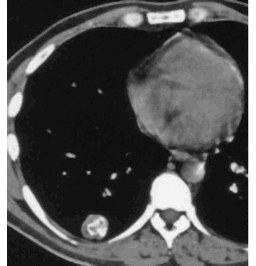

SHAPE - round

MARGIN - smooth

SIZE - 2.5 cm

DENSITY - contains central calcification, clearly seen on these windows (soft tissue)

NOTE: any round lung opacity that is less than 3 cm in diameter should be called a 'NODULE' - some patterns of calcification, like this, indicate a BENIGN etiology